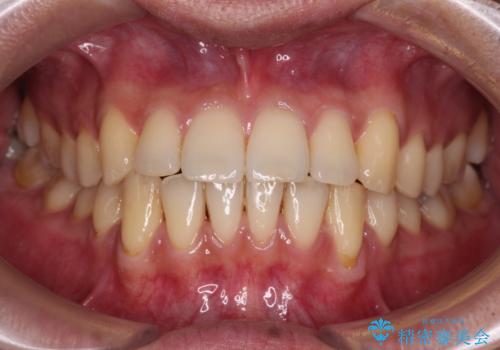

ディープバイトと叢生 インビザラインによる矯正治療

- 前歯のディープバイトと叢生を気にして来院された患者様です。

ディープバイトもデコボコも改善され、気になっていた銀歯もセラミックとなり、患者様には大変満足していただきました。